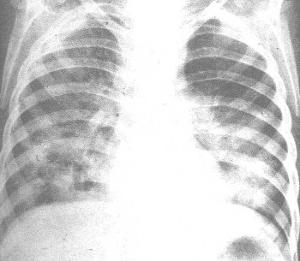

与年轻人比较,老年肺炎的发病率和死亡率均显著增加的原因是多方面的,客观上,因机体老化,呼吸系统解剖和功能的改变导致全身和呼吸道局部的防御和免疫功能降低,心肺肝肾等重要脏器的功能储备减弱或罹患多种慢性严重疾病、营养不良等;主观原因则是医生或患者自己对老年肺炎的不典型临床表现认识不足,诊断延误和治疗措施不当。[1]